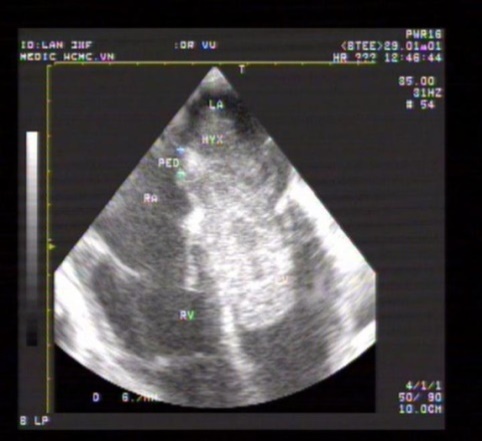

Cardiac myxomas in our study develop in the LA, pedunculated and attached to IAS. Three-dimensional ( 3D )TEE shows the location, the size, the mobility and the stalk of myxoma on Live 3D and Full volume.

Three dimensional 3DTEE can study the obstruction of mitral orifice caused by protruding myxoma [1-10].

Tumor of the RV and Fibroblastoma of aortic cups were noted in our study (Figures 38-43).

Figure 38. Giant myxoma seen on 2DTEE

Figure 39. 2DTEE multiplane at 135⁰ shows  LA myxoma

Figure 40. LA myxoma visualized on 3DTEE Live mode